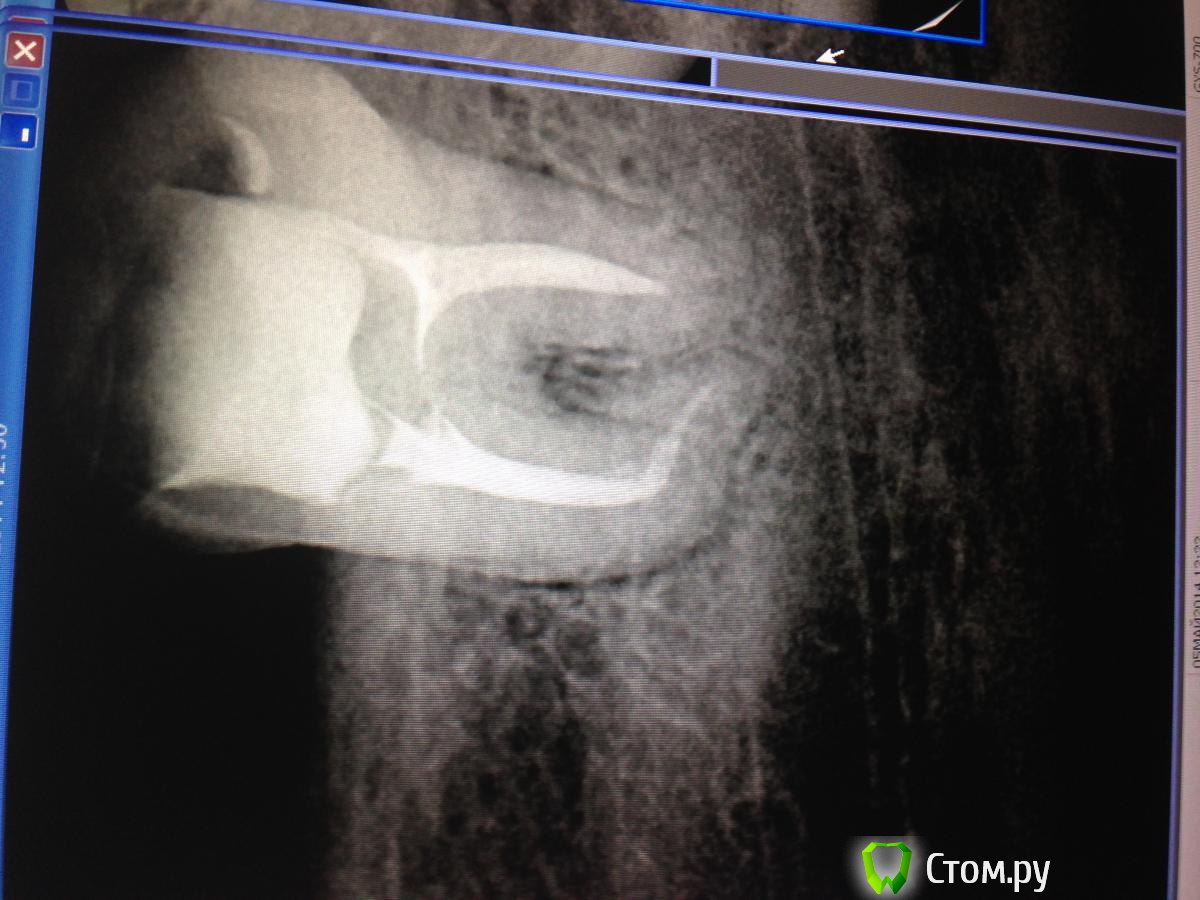

SSTi Опубликовано 20 мая, 2014 Автор Поделиться Опубликовано 20 мая, 2014 пульпитный 35. с сюрпризом в виде кривульки. Доступ дистально. коффер, обработка ручными к-файлами, машинные протейперы( до ф2), профайлы. Много гипохлорита, уз.Все время было чувство, что сломаю файл за изгибом, или нарежу ступень... но пронесло)) боялся, что не дойду до апекса(апекслокатор не начинал пока даже попискивать), потом дошел, отступил 0,5, сделал упор и вот тебе результат- вышел на 0,5.... 8 Ссылка на комментарий

SSTi Опубликовано 20 мая, 2014 Автор Поделиться Опубликовано 20 мая, 2014 кстати он находится на месте 7ки, а 36 на месте 38. между 35 и 34 сантиметра 1,5-2.3,7 и 3,8 нет Ссылка на комментарий

SSTi Опубликовано 20 мая, 2014 Автор Поделиться Опубликовано 20 мая, 2014 (изменено) Спасибо)Я никогда не забуду хруст протейперов в этой пятерке и мысли о том, как доставать если вдруг ...))) что-то везет в последнее время на кривули такие. Кстати рд здесь-25.5 мм. Напрягает, когда эндонаконечник вплотную к зубу и ты не видишь файла..... Изменено 20 мая, 2014 пользователем SSTi Ссылка на комментарий